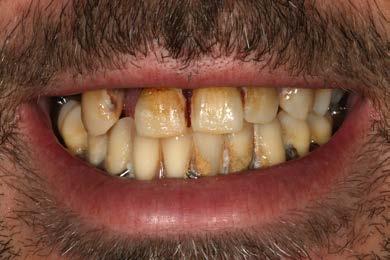

Figura 7 Cone-beam de control de la zona más distal del primer cuadrante donde se planifica un implante extracorto

Presentamos el caso de un paciente de 35 años, fumador, con enfermedad periodontal agresiva en fase avanzada y un deficiente control de la higiene oral. El paciente acude a nuestro centro solicitando un tratamiento restaurador con implantes dentales, tras haber experimentado varios fracasos con prótesis removibles previas. Durante la exploración intraoral, se observa periodontitis avanzada, con una significativa pérdida de inserción en la mayoría de los dientes, un control inadecuado de la placa bacteriana, y una prótesis removible mal ajustada anclada a dientes con movilidad (Figura 1 y 2). En la radiografía panorámica inicial podemos constatar la gran pérdida ósea horizontal, en todas las piezas dentales, con algunas de ellas ancladas únicamente en el tejido gingival. Además vemos también en la imagen

cómo existen varias piezas dentales con pronóstico dudoso con grandes caries con afectación radicular que deben ser extraídas, como los molares de los sectores posteriores maxilares, tanto derecho como izquierdo (Figura 3).

En la primera fase de tratamiento, se procede a la extracción de las piezas dentales con un pronóstico irrecuperable, regenerando los alveolos con PRGF-Endoret. Además, se decide conservar dientes clave en ambos arcos, que servirán para la colocación de prótesis provisionales apoyadas en ellos durante la fase inicial de cicatrización tras las extracciones, permitiendo también el mantenimiento de la propiocepción. En este proceso, se preservan los caninos superiores e inferiores, que son preparados para soportar la prótesis provisional, junto con 2 molares inferiores (37 y 46) que presentan buen pronóstico.

Para elaborar la planificación de los implantes a colocar se realiza en primera instancia un TAC, observándose en el mismo que existe un déficit de altura en todo el maxilar superior.

Todos los dientes conservados reciben un mantenimiento periodontal riguroso (Figura 4-6). Transcurridos 2 meses, comenzamos con la rehabilitación del maxilar superior mediante implantes. Durante este tiempo se lleva a cabo la inserción y rehabilitación provisional mediante prótesis de carga inmediata de la mandíbula. Para elaborar la planificación de los implantes a colocar se realiza en primera instancia un TAC, observándose en el mismo que existe un déficit de altura en todo el maxilar superior, siendo más acusada la atrofia en altura en la zona de los molares. En el primer cuadrante, tenemos una altura ósea de 5.5 mm por lo que podemos planificar la colocación de un implante extracorto (5.5 mm de longitud y 5.5 mm de diámetro) con elevación de seno transcrestal (Figura 7). En el segundo cuadrante, existe una atrofia ósea en altura mucho mayor con menos de 1 mm de altura, existiendo áreas donde se produce una ruptura

en la continuidad de este reborde óseo, por lo que la mejor alternativa terapéutica es la realización de una elevación de seno mediante abordaje lateral (convencional) (Figura 8).

Transcurridos 6 meses desde la elevación de seno convencional, ya podemos llevar a cabo la colocación de los implantes, una vez madurado el injerto óseo. En el cone-beam de control realizado en este momento,

observamos cómo tenemos altura ósea suficiente para su inserción y optamos por la colocación de un implante de 7.5 mm de longitud y 5.5 mm de diámetro (Figura 9). El uso de este diámetro nos asegura una estabilización tridimensional óptima en el lecho receptor, minimizando la aparición de micromovimientos durante la fase de integración. En cuanto a la longitud del implante, aunque sería viable utilizar uno más

largo, no lo consideramos necesario. Con una longitud de 7.5 mm es suficiente para garantizar un comportamiento biomecánico estable a largo plazo, además de que esta opción nos permite ser más conservadores con el lecho óseo neoformado receptor. En esta misma fase quirúrgica se realiza la segunda cirugía de los implantes del primer cuadrante colocados mediante la elevación transcrestal en

la fase quirúrgica previa y se cofecciona una prótesis de carga progresiva, aún sin englobar el implante colocado en la elevación de seno del segundo cuadrante. La prótesis se confecciona sobre transepiteliales, atornillada y se elabora con barras preformadas, por lo que puede generarse pocas horas después de la segunda fase y la toma de medidas. En este momento se decide la exodoncia de los caninos

superiores e inferiores, ya que han empeorado periodontalmente. (Figura 10).

La prótesis de carga progresiva superior, se mantiene durante 5 meses. Posteriormente, con el patrón oclusal estable se procede a la carga del último implante del segundo cuadrante (el insertado en la elevación de seno convencional) y se realiza la prótesis definitiva. Para la realización de esta prótesis, se confecciona un encerado que puede ser probado en boca y una vez ajustado puede ser escaneado para la confección digital de la prótesis. La estructura se diseña y se

Las prótesis tanto para los implantes colocados en el primer cuadrante (elevación transcrestal) como para el segundo cuadrante (elevación convencional), son confeccionads con una estructura metálica fresad por CAD-CAM con la adición final de la cerámica de forma tradicional y se dividen en 3 sectores (posterior derecho, central y posterior izquierdo). Finalmente, solo pueden ser conservados los molares inferiores, pero son suficientes para que aporten al paciente una propiocepción

cómo ha cambiado completamente la oclusión, la estética y la salud de los tejidos gingivales.

correcta en los movimientos masticatorios. Mantener piezas dentales nos posibilita la consecución de una propiocepción efectiva y aumenta del valor que tiene para un paciente desde un punto de vista psicológico la conservación de parte de su dentición natural.15-16,22 Una vez finalizada la rehabilitación protésica, el paciente continúa en seguimiento activo, con mantenimiento periodontal y periimplantario, inicialmente cada 3 meses y posteriormente al año de seguimiento espaciando las visitas de control cada 6 meses. Durante todo el seguimiento (4 años) la estabilidad ósea entorno a los implantes dentales, se mantiene estable, así como en los molares remanentes (Figura 13-16). Ambas técnicas por lo tanto (elevación transcrestal y elevación de seno convencional) han obtenido un resultado muy similar por lo tanto en el paciente reportado, con EP

agresiva, siendo buenas opciones de tratamiento, aunque cada una con sus indicaciones en función del volumen óseo residual como hemos comentado en el inicio del artículo.